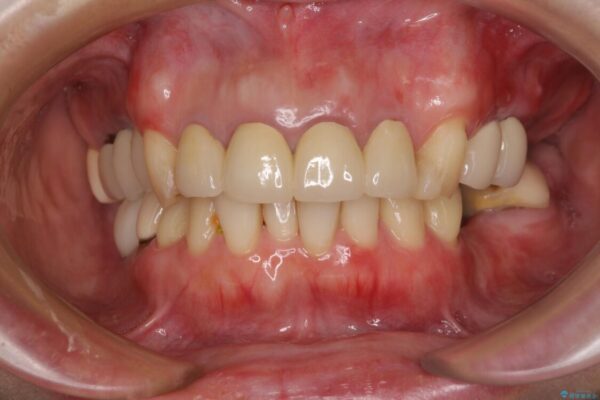

治療後

• 仮歯のまま放置した前歯 オールセラミッククラウンで自然な前歯に 治療後画像

治療後について

日頃の歯磨きをしっかりと行ってくださるので、新しい仮歯に変えてから速やかに歯肉の状態が改善されました。

歯肉からの出血がほとんどないため精度の良い型取りができ、非常に適合の良い補綴治療を行うことができました。